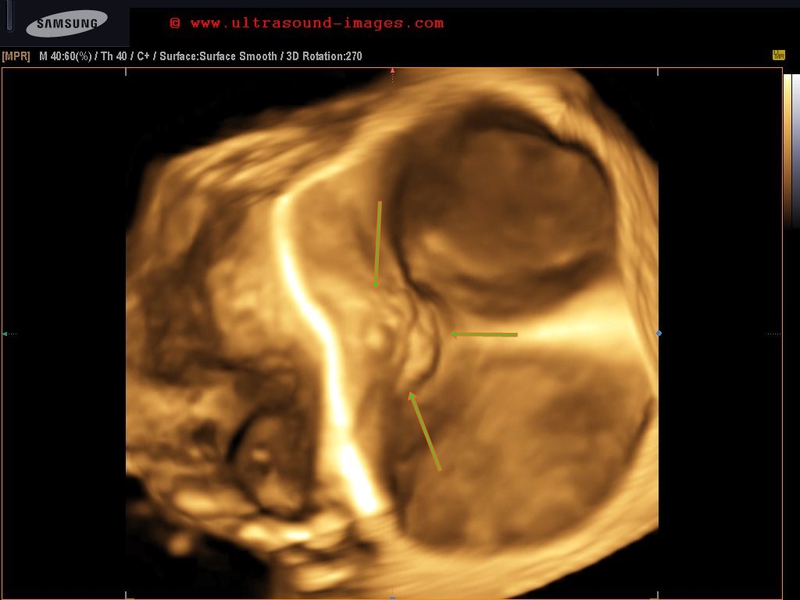

Case-3: Ring calcification of uterine fibroid

Fibroids can also show a complete ring of calcification, as in the ultrasound images shown in case-3 above. The fibroid shows a dense peripheral calcific rim, within the intramural mass that occupies the fundus and body of the uterus. The ultrasound image on the right is a 3D rendering of the calcific ring in the fibroid. The striking resemblance to a fetal head is amazing. Images are courtesy of Dr. Ravi Kadasne, MD, UAE.